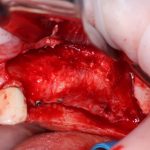

Разрез и скелетирование альвеолярного гребня.

Разрез, он как почерк. Это отражение вашего понимания ситуации, вашего характера, если хотите. Разрез должен быть максимально рациональным: с одной стороны, чем он меньше. тем лучше:

Однако, синуслифтинг — это та операция, которая требует очень хорошего обзора операционного поля. Поэтому, если вдруг чувствуете, что размеров разреза не хватает, не бойтесь его расширять. Ибо во время этой операции делается очень много ошибок по одной лишь причине — кто-то что-то очень-очень плохо видел.

Если нет задачи ставить импланты — зачем открывать и скелетировать альвеолярный гребень? Чем больше операционная рана, тем больше потом будет проблем. Будьте рациональны:

Как видите, я перенес разрез вестибулярно, примерно в проекции предполагаемого субантрального доступа. Таким образом, я получаю тот же обзор при меньшей по площади ране. Это безопаснее. Такой доступ очень просто и легко зашивается, рана заживает быстрее и с минимальным дискомфортом. Кроме того, слизистая оболочка вершины альвеолярного гребня, где мы будем потом делать следующий разрез для установки имплантов, осталась неповрежденной, мы не оставили на ней рубцов, которые могут осложнить заживление при повторном входе для установки имплантов.